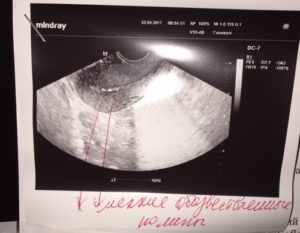

Данный вид исследования в кругу врачей считается более точным. Обычно именно он назначается для изучения состояния органов малого таза. Возможным считается также его применение при беременности на ранних сроках.

По результатам вагинального УЗИ можно выяснить стадию развития плода, рассмотреть самые незначительные аномалии и выяснить причину повышенного тонуса живота. Насколько необходимо проведение этой процедуры на маленьком сроке, решает непосредственно врач. Обычно это связано с какими-то патологиями, заболеваниями матери или проявлении негативных симптомов (кровотечение, боли внизу живота).

Таким методом допускается проводить изучение состояния плода на сроке до 12 недель. При этом в совокупности с анализами (мазками) он даст более точную картину. Однако большинством женщин процедура признается довольно неприятной, поэтому без указания на то гинеколога, ее обычно не проводят.